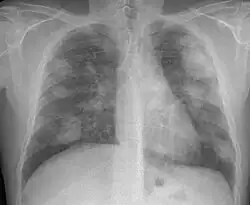

There are three key elements to the diagnosis of silicosis. First, the patient history should reveal exposure to sufficient silica dust to cause this illness. Second, chest imaging (usually chest x-ray) that reveals findings consistent with silicosis. Third, there are no underlying illnesses that are more likely to be causing the abnormalities. Physical examination is usually unremarkable unless there is complicated disease. The examination findings are not specific for silicosis.[20]

For uncomplicated silicosis, chest x-ray will confirm the presence of small (< 10 mm) nodules in the lungs, especially in the upper lung zones. Using the ILO classification system, these are of profusion 1/0 or greater and shape/size "p", "q", or "r". Lung zone involvement and profusion increases with disease progression. In advanced cases of silicosis, large opacity (> 1 cm) occurs from coalescence of small opacities, particularly in the upper lung zones.

With retraction of the lung tissue, there is compensatory emphysema. Enlargement of the hilum is common with chronic and accelerated silicosis. In about 5–10% of cases, the nodes will calcify circumferentially, producing so-called "eggshell" calcification. This finding is not pathognomonic (diagnostic) of silicosis. In some cases, the pulmonary nodules may also become calcified.

Complicated silicosis -

- Complicated silicosis

- Silicosis can become "complicated" by the development of severe scarring (progressive massive fibrosis, or also known as conglomerate silicosis), where the small nodules gradually become confluent, reaching a size of 1 cm or greater. PMF is associated with more severe symptoms and respiratory impairment than simple disease. Silicosis can also be complicated by other lung disease, such as tuberculosis, non-tuberculous mycobacterial infection, and fungal infection, certain autoimmune diseases, and lung cancer. Complicated silicosis is more common with accelerated silicosis than with the chronic variety.